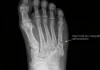

L’orteil en griffe est une déformation courante du pied. Les orteils se plient dans une position semblable à une griffe. Cette malposition des orteils aura comme conséquence qu’ils creuseront dans la semelle des chaussures, créant des callosités douloureuses sur le dessus ou le bout des orteils.

- La difformité des orteils en griffe causera les malpositions suivantes:

- Extension de l’articulation métacarpophalangienne

- Flexion des articulations proximale et distale interphalangienne